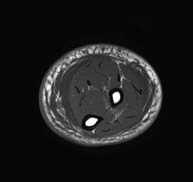

Exploració ideal per estudiar les lesions en músculs isquiotibials i quàdriceps, sovint lesionats en esportistes. També permet una bona valoració de tendons i de nervis perifèrics. La durada aproximada és de 20 minuts. No utilitza radiació ionitzan. - RM de Genoll

Exploració per estudiar lesions a l'articulació, com trencaments dels meniscals i dels lligaments creuats (únicament es poden detectar amb aquesta prova), condropatia o desgast del cartílag i moltes altres alteracions derivades de l'activitat esportiva i dels canvis degeneratius (osteoartrosi). La durada aproximada és de 18 minuts. No utilitza radiació ionitzant. - RM de Cama

Exploració per estudiar lesions a tendons, a músculs i a nervis perifèrics. És de gran utilitat per diagnosticar ruptures fibrilars als bessons. La durada aproximada és de 18 minuts. No utilitza radiació ionitzant. - RM de Turmell